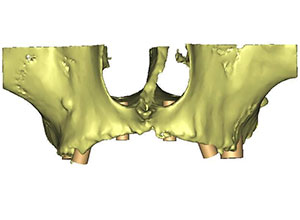

La tomografía se transporta a un estudio 3D, en donde se encuentra un maxilar sumamente atrófico, con muy poco soporte de hueso y se procede a hacer el plan de tratamiento en este estudio 3D.

Se muestran imágenes del estudio 3D con la colocación de 6 implantes de titanio en el maxilar superior que se colocarán de forma especial para levantar la parte del seno maxilar y colocar injertos de hueso. Estos 6 implantes quedarán colocados en una forma oblicua, de tal manera que se van a necesitar aditamentos especiales multidireccionales con el objetivo de colocar al final una prótesis fija, la finalidad y el objetivo principal es terminar el tratamiento con una prótesis completamente fija.